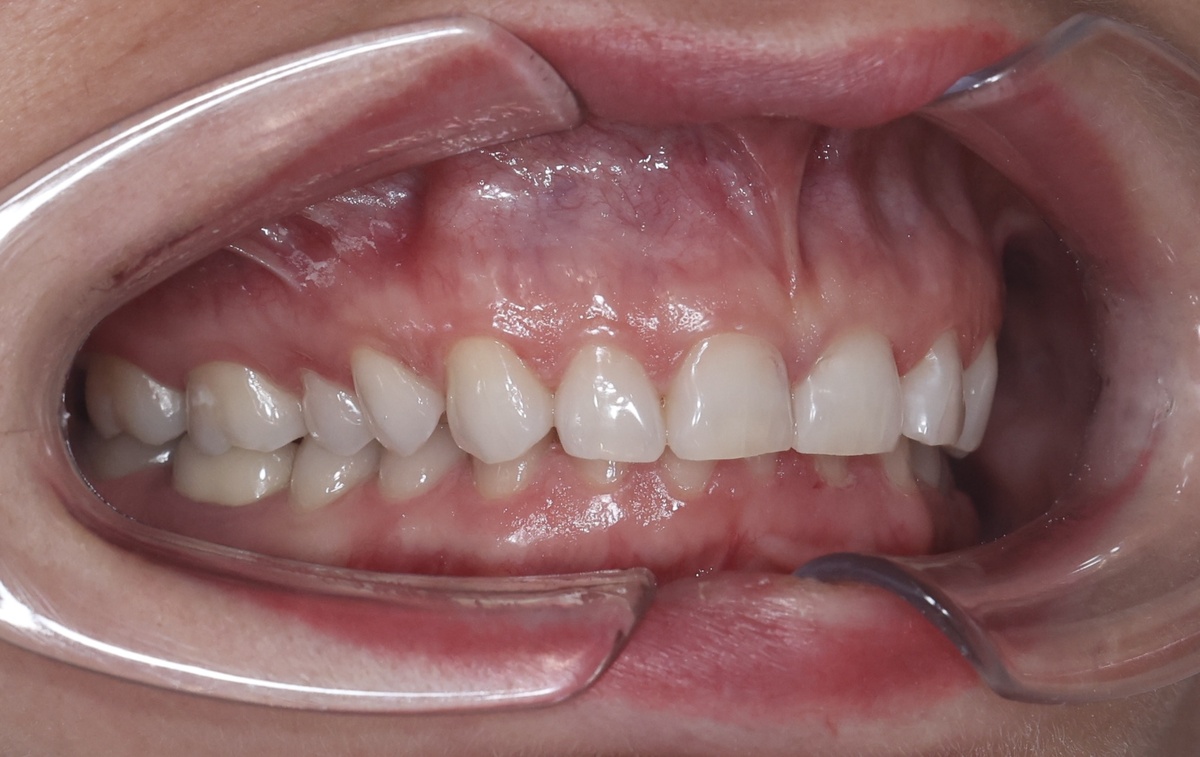

Мой прикус до исправления - жуть